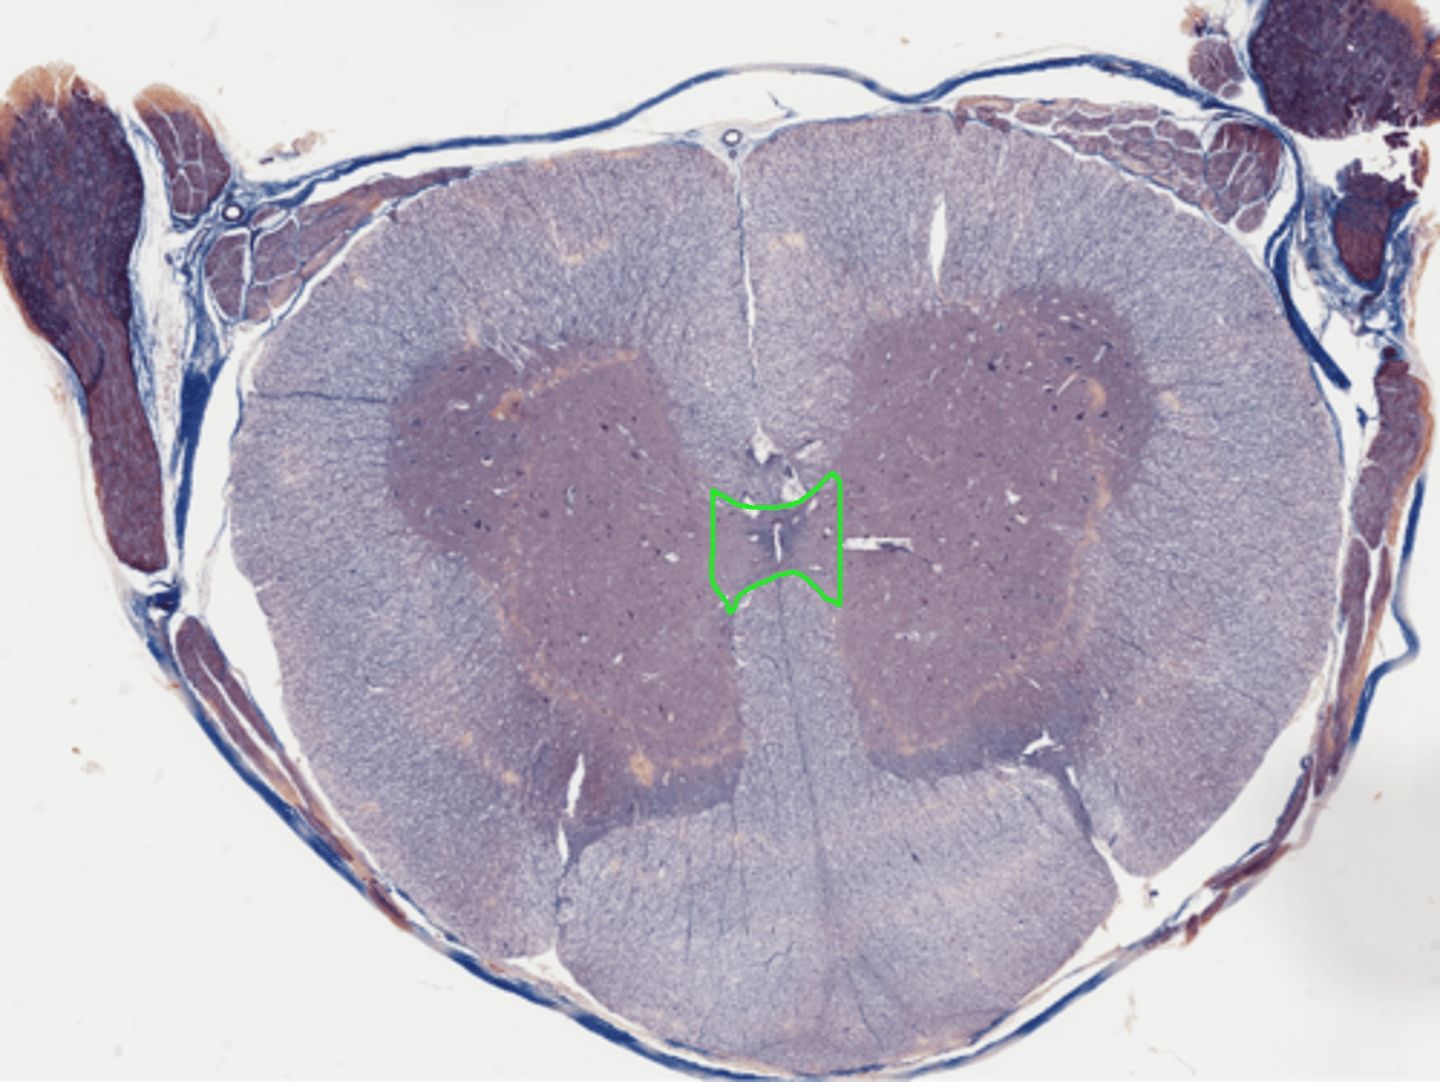

gray commissure

central canal